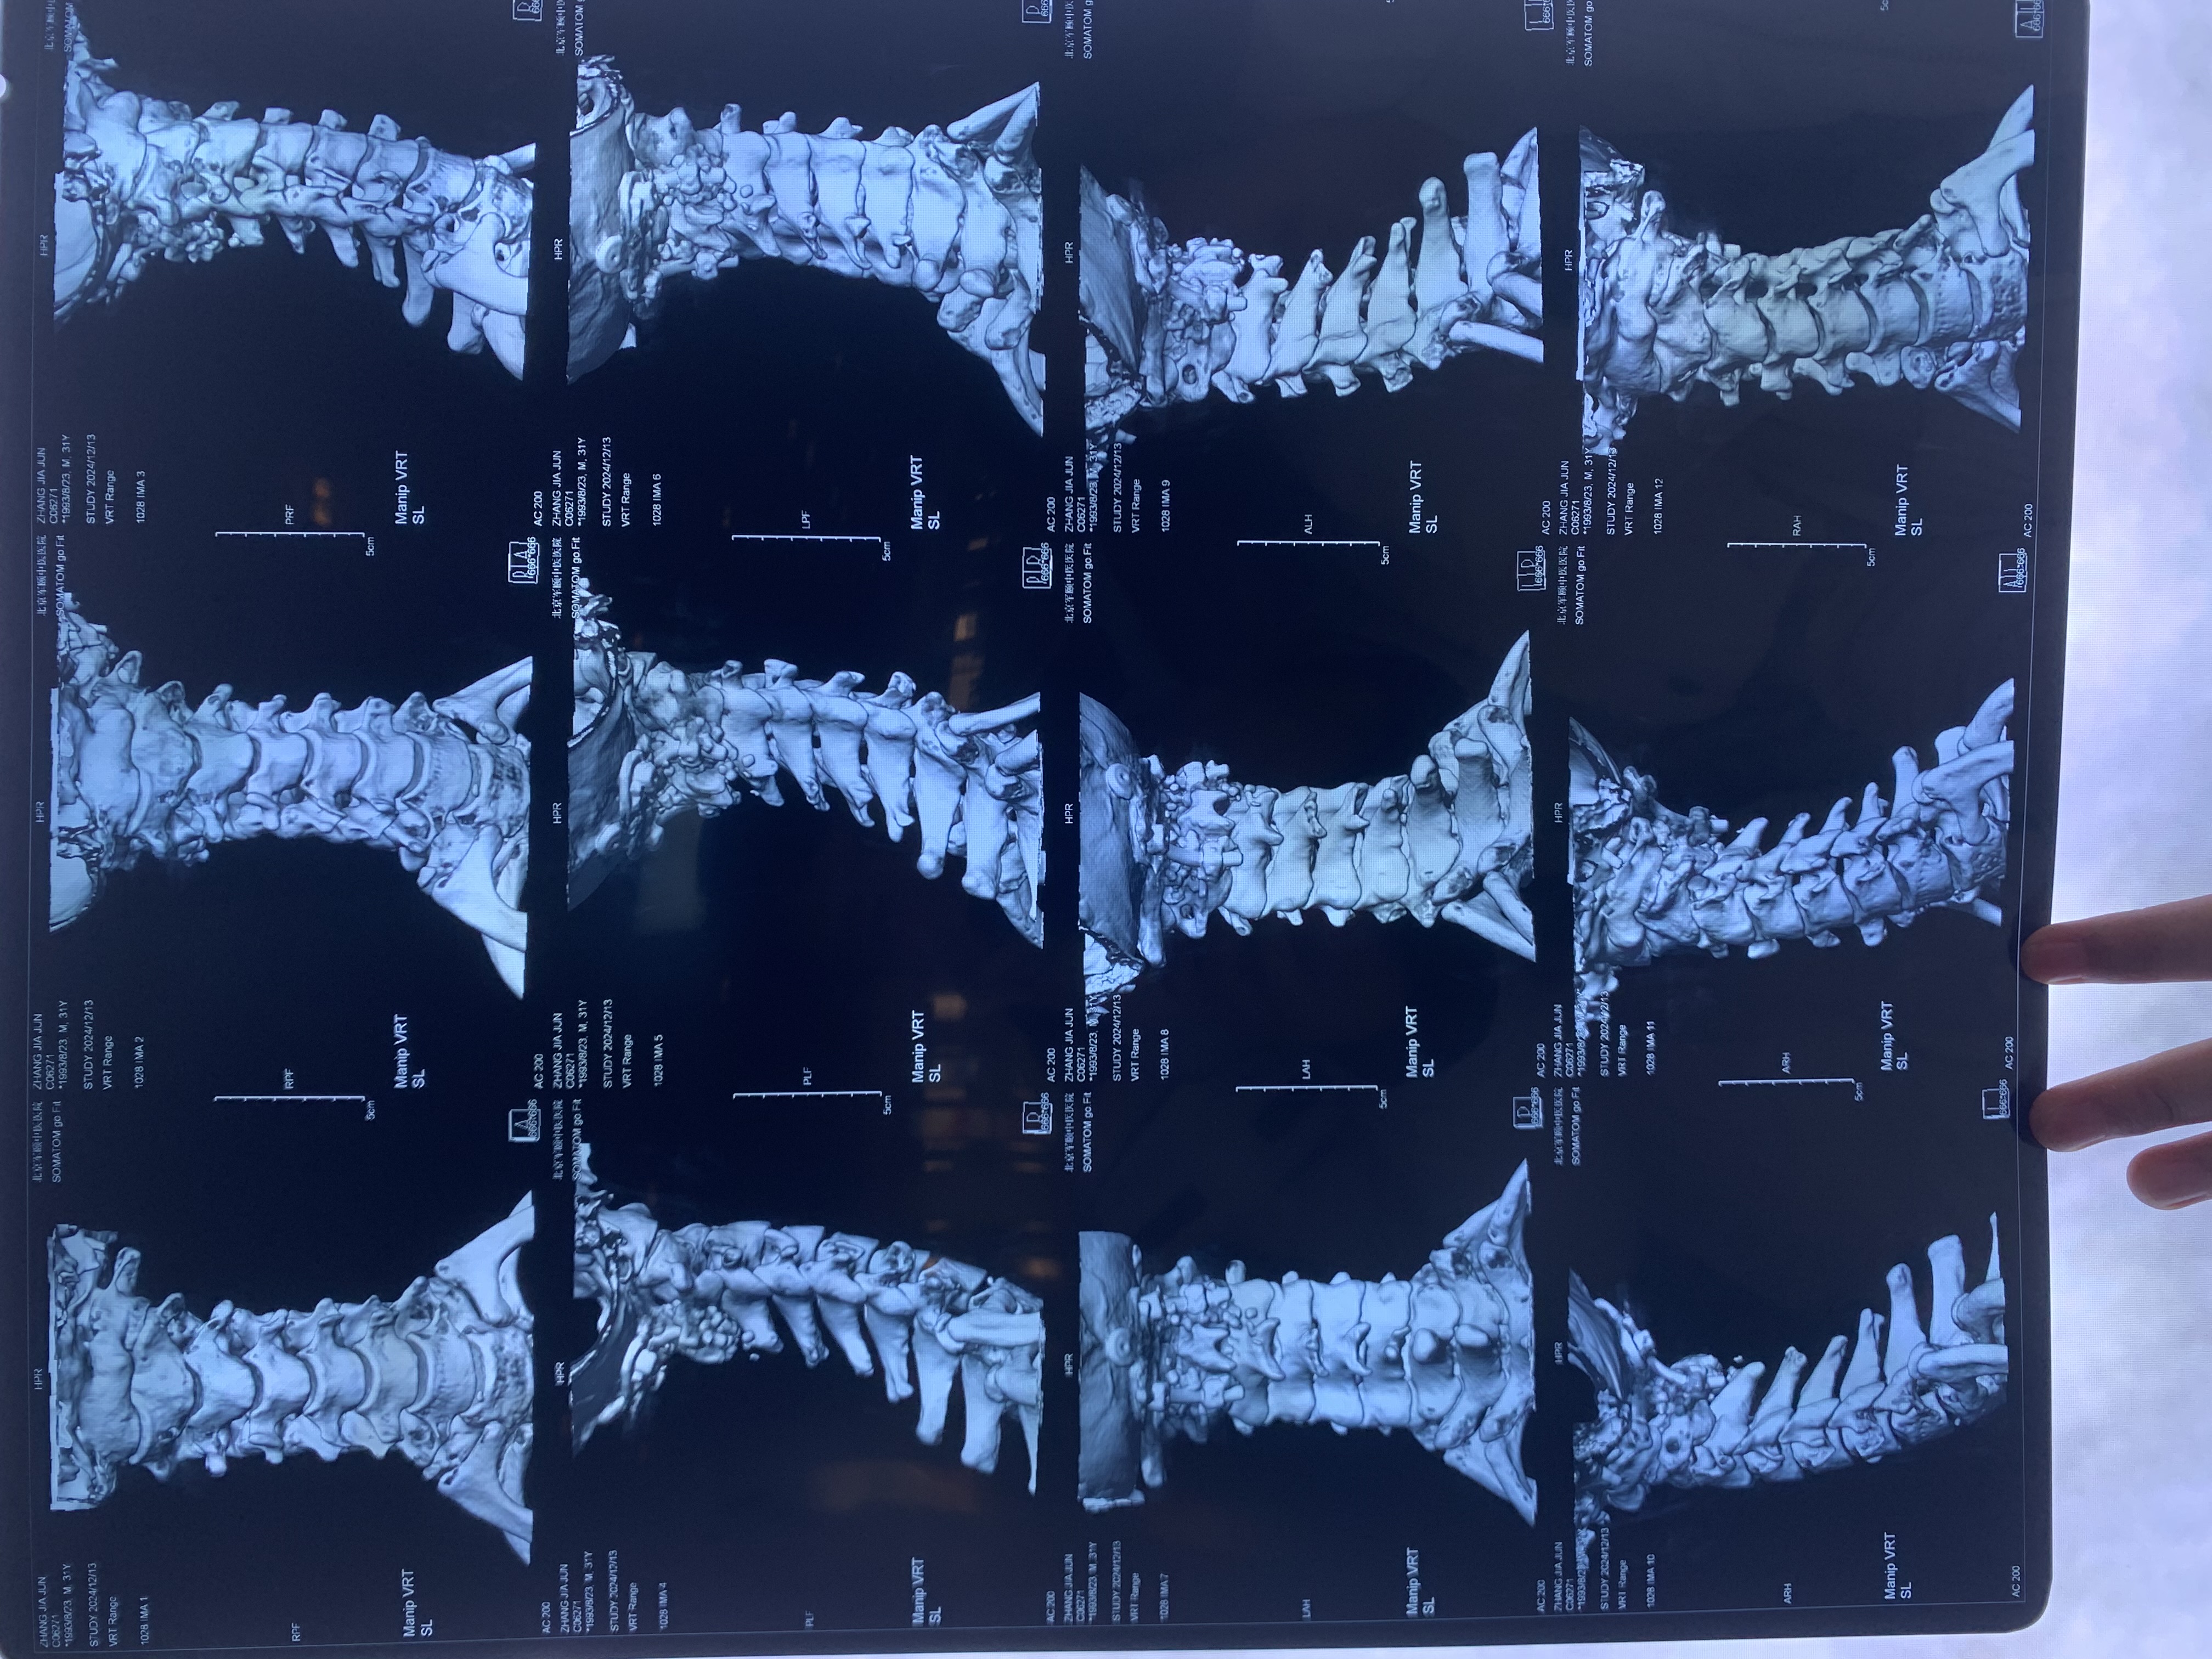

• 2024.12.13,去北京拍片,当天走路有点多,感觉脑袋里面疼。影像报告脱位和颅底凹陷都还在,影像如下: